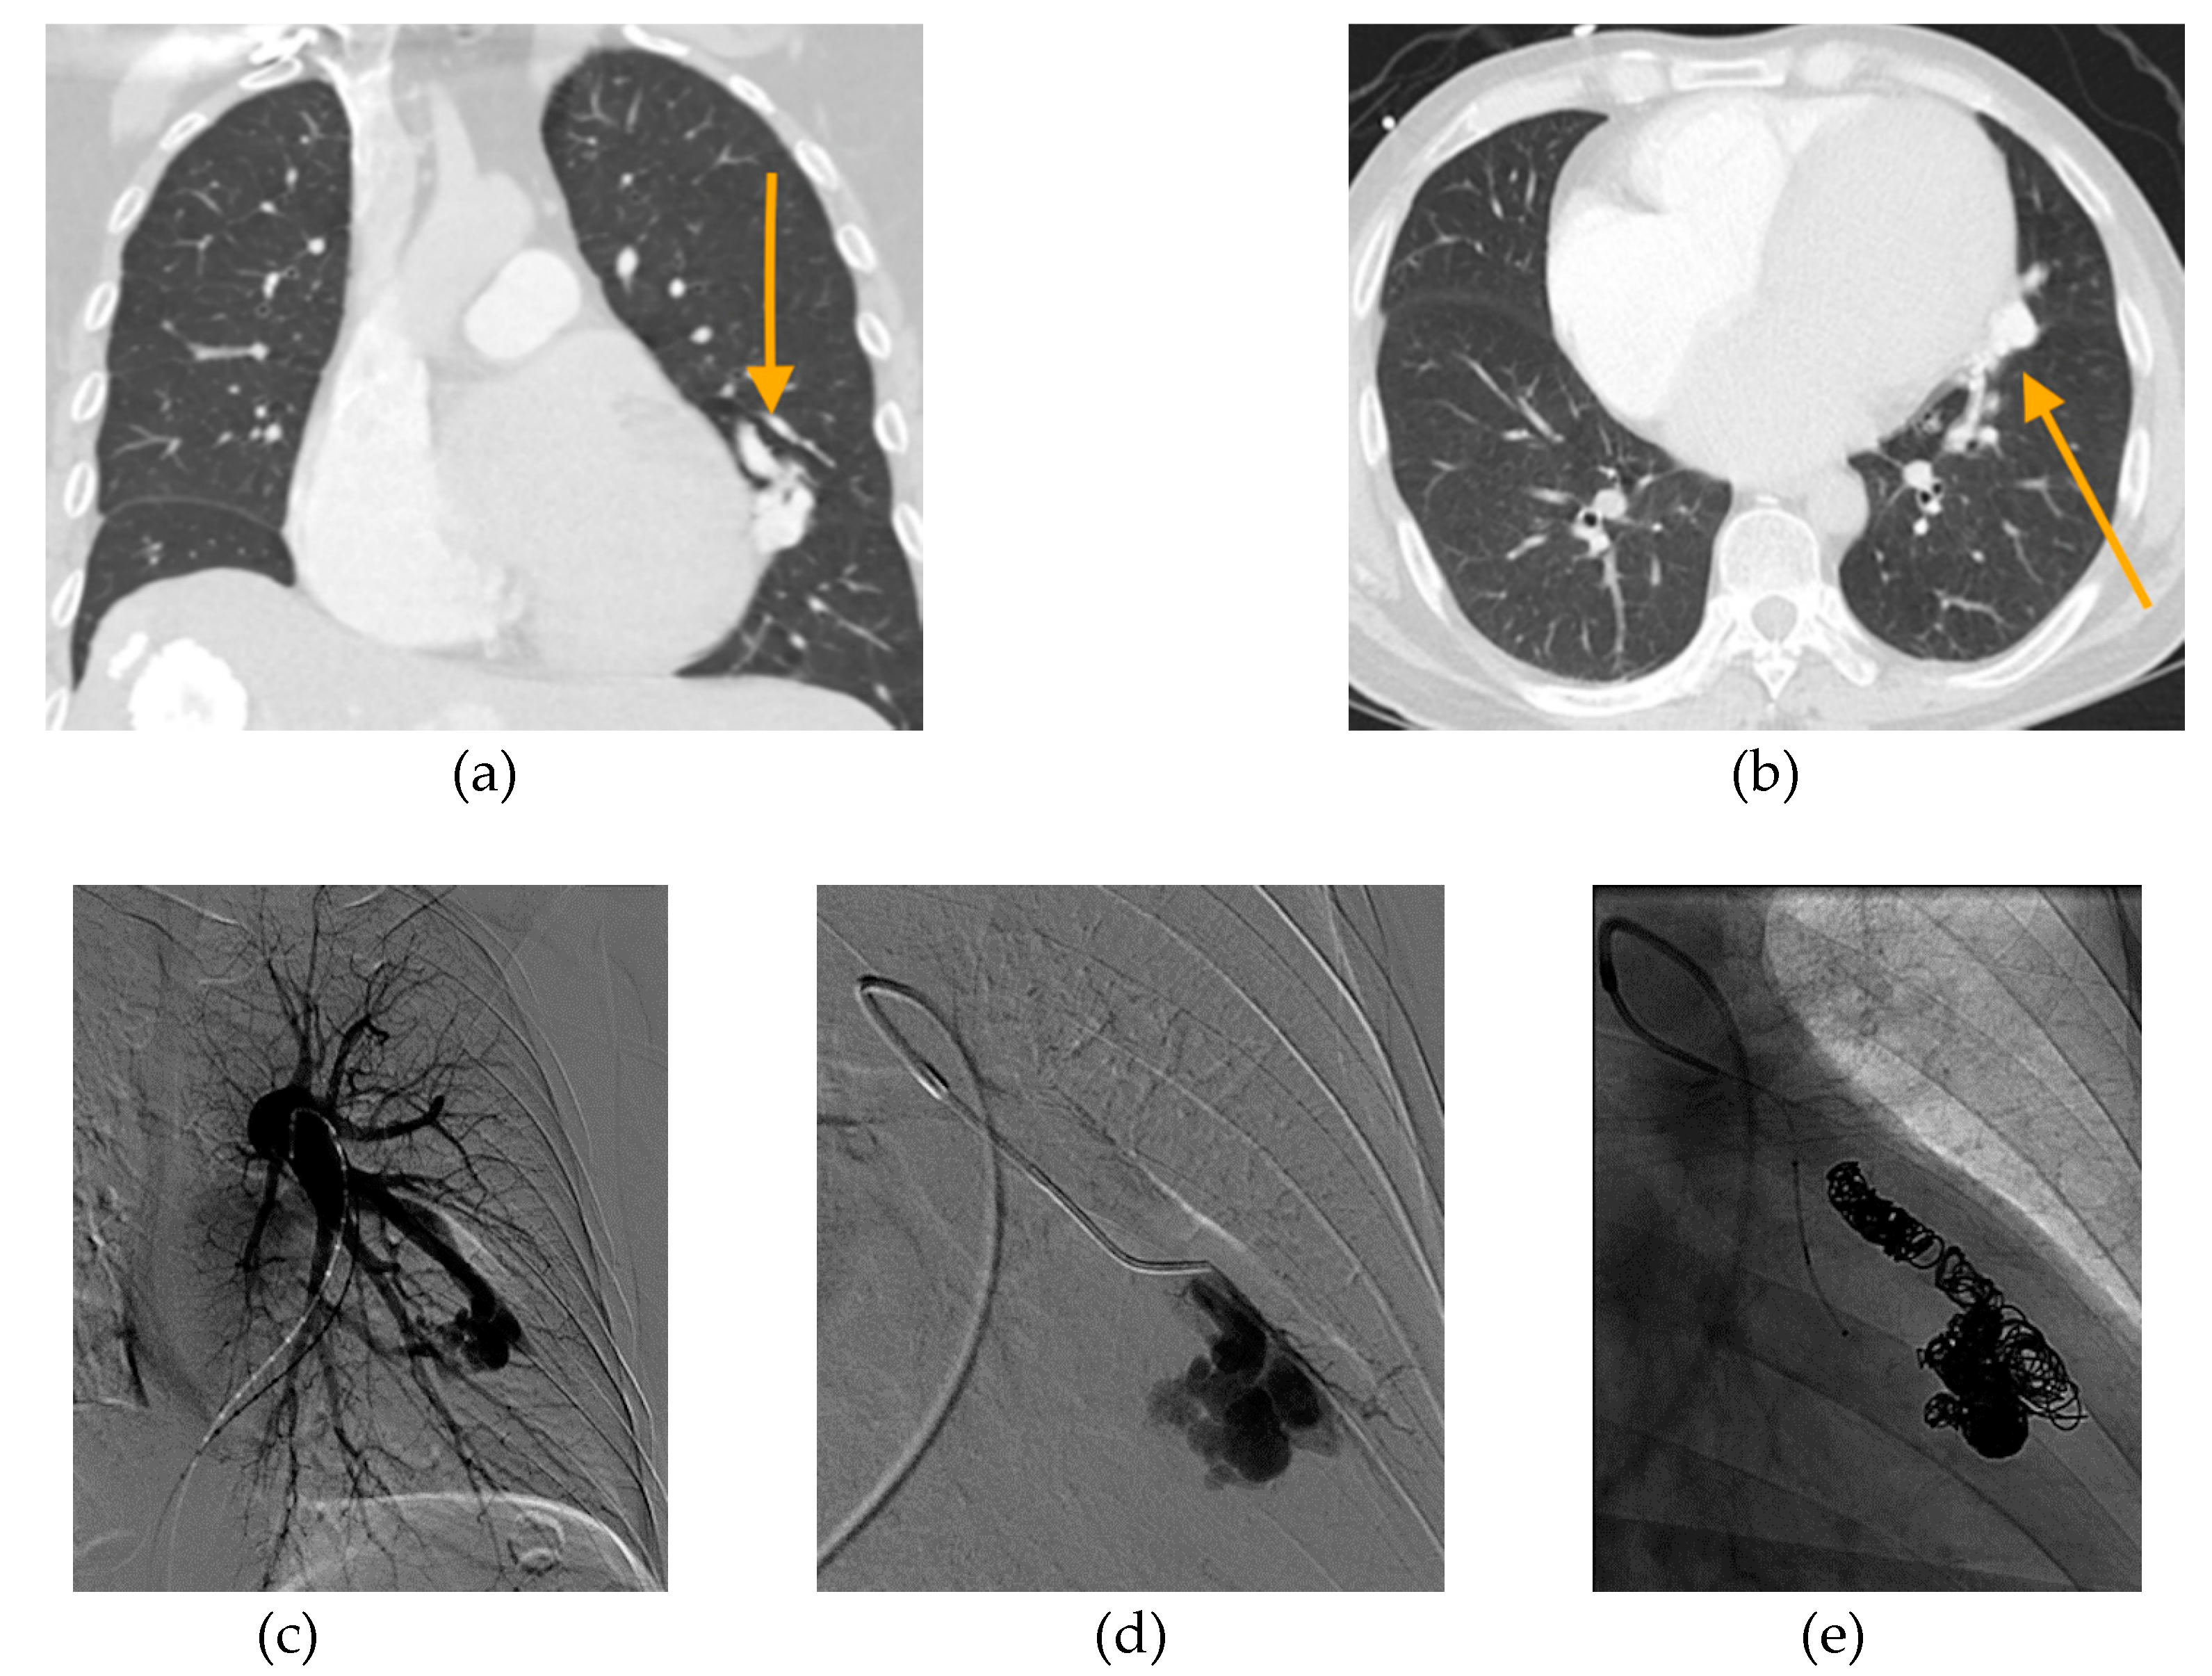

Figure 5.

49-year-old male with history of nonischemic cardiomyopathy, severe mitral and triscuspid regurgitation, PAVM, and PH presented with acute hypoxemic respiratory failure. (a) Axial and (b) coronal CT angiogram images revealing a large PAVM in the lingula (orange arrows). (c) Initial pulmonary angiogram of the left lung demonstrates that a large proportion of pulmonary arterial flow passes through the PAVM, acting as a “pop-off” valve. (d) Selective angiogram shows selection of the feeding artery with filling of the complex PAVM sac. Prior to embolization, patient’s oxygen saturation on 4 L nasal cannula was 89%. Pre-embolization main pulmonary artery pressure (PAP) was 53/21 mmHg (mPAP 33 mmHg). (e) Final pulmonary angiogram shows occlusion of PAVM with combined coiling and deployment of an 8 mm Amplatzer plug in the arterial feeder. Following embolization, PAP increased 72/37 mmHg (mPAP 50 mmHg). Oxygen saturation on 4 L nasal cannula improved to 99%. The patient was weaned to room air and discharged in good condition. Two years later, he was admitted on multiple occasions for acute decompensated heart failure. At 3.5 years after embolization, he died from acute renal failure secondary to cardiorenal syndrome.